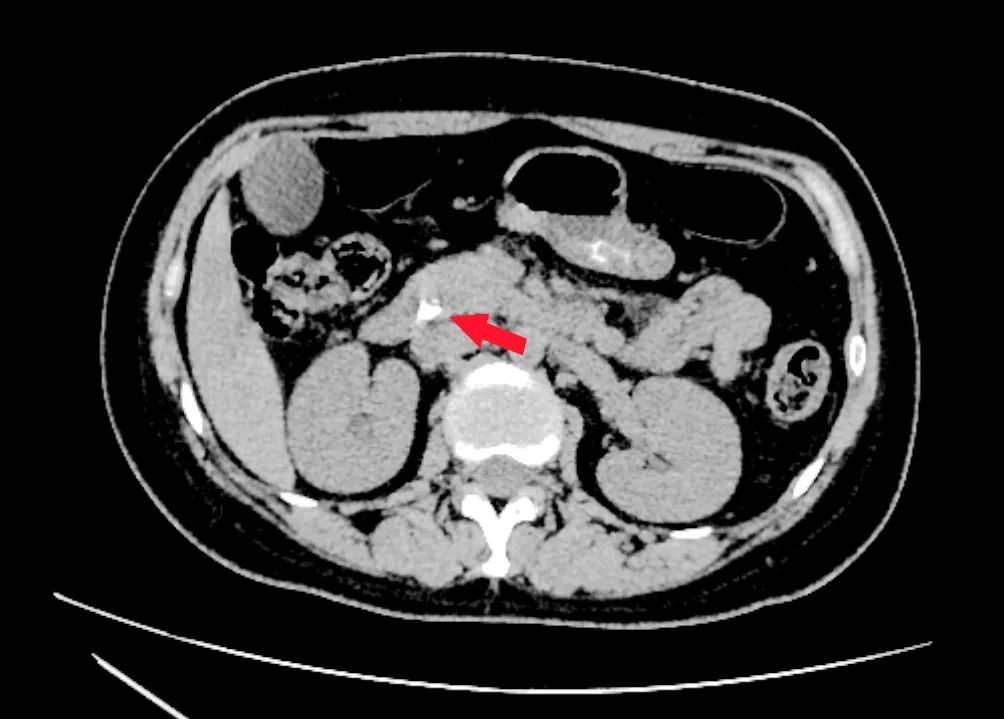

患者为年轻女性,反复腹痛3天入院,腹部CT显示:胆总管下段结石、肝内外胆管轻度扩张;肝功能多项指标明显升高。经保守治疗后,患者腹痛症状仍反复。李捷壮主任医师、刘烈辉副主任医师带领的ERCP团队对患者做了详细的体格检查、仔细判读相关辅助的检查,明确诊断:胆总管下段结石伴胆管炎。经过全面的术前讨论及科室团队反复商酌,决定为患者实施“经内镜逆行胰胆管造影+胆总管结石取出术”治疗。

▲术前CT